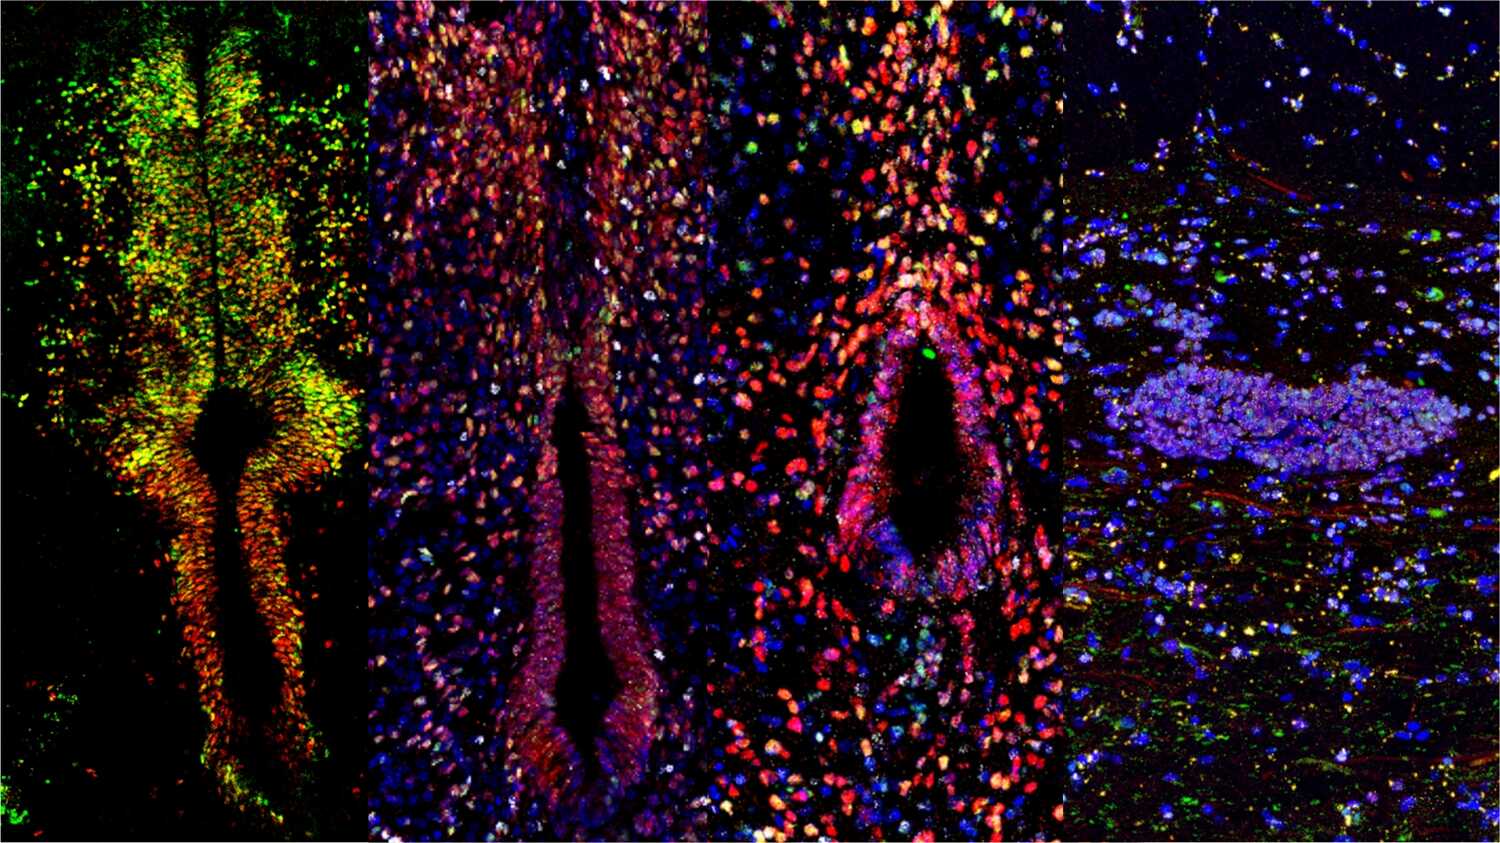

Study Unveils Differential Lineage Plasticity of Ependymal Cells and Astrocytes in Spinal Cord Injury Repair

Researchers led by Profs. DAI Jianwu and ZHAO Yannan from the Institute of Genetics and Developmental Biology of the Chinese Academy of Sciences explored the regenerative mechanisms behind spinal cord injury repair.

Researchers Unlock Craniopharyngioma Growth Mechanism and Identify Potential New Therapy

Researchers from Professor WU Qingfeng’s lab at the Institute of Genetics and Developmental Biology of the Chinese Academy of Sciences, identified a promising targeted therapy for craniopharyngioma through advanced animal modeling and high throughput drug screening.